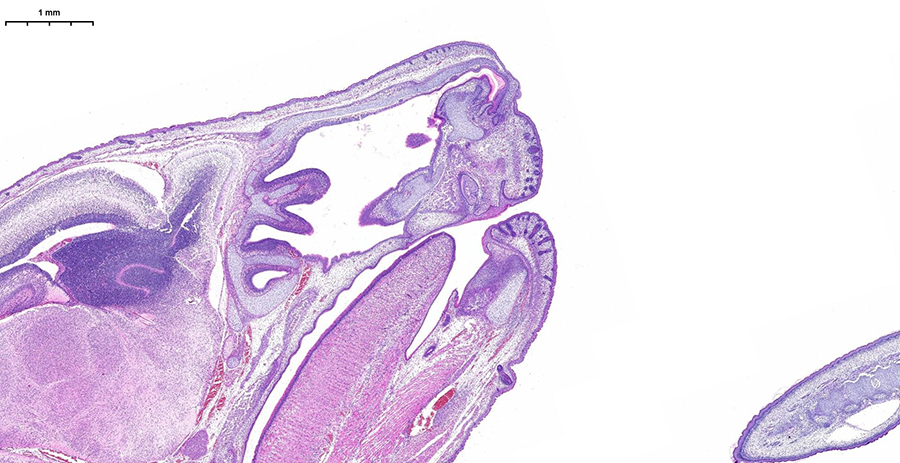

Погрузитесь в будущее гистологической лаборатории на двухдневном мероприятии, где представится возможность поработать с новейшим гистосканером LG-S80 от Servicebio.Погрузитесь в будущее гистологической лаборатории на двухдневном мероприятии, где представится возможность поработать с новейшим гистосканером LG-S80 от Servicebio.

Сможете оценить высочайшее разрешение, скорость обработки (полное стекло за 3-5 минут) и интеллектуальное аналитическое ПО, которое автоматически распознаёт структуры и формирует количественные отчёты с готовыми данными. Можно принести для апробации свои образцы, демонстрируемая конфигурация флуоресцентных каналов (Ex/Em, нм):